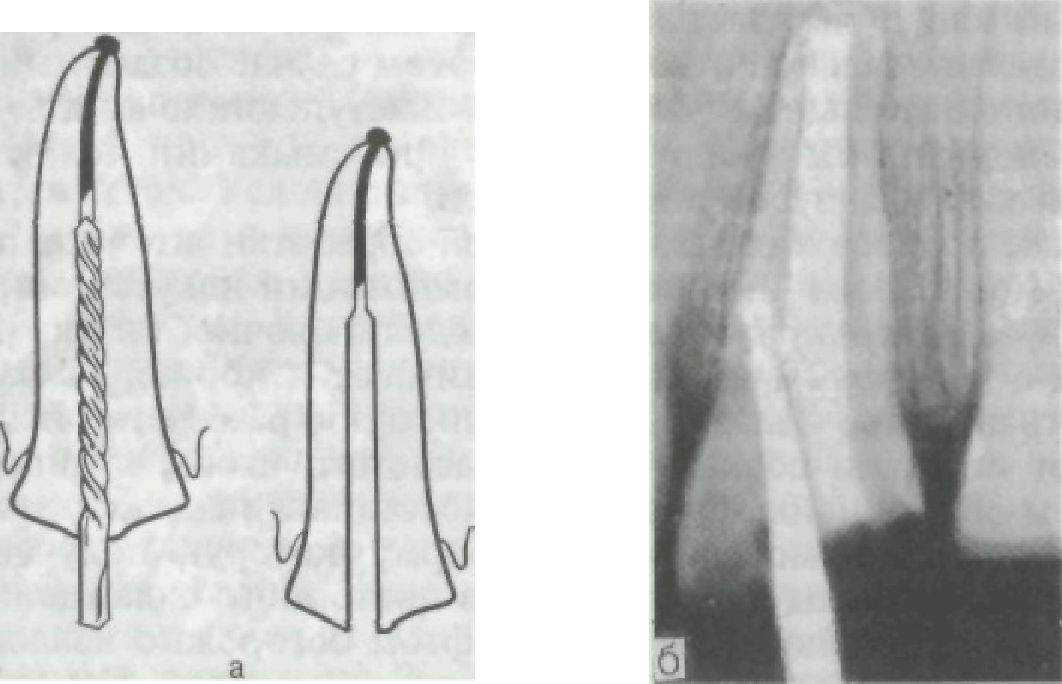

Рис. 82. Основные виды современных штифтовых зубов. а — культевая штифтовая вкладка и ее разновидности; б — по Ричмонду; в — цельнолитой с облицовкой.

Рис. 83. Правильное (а) и неправильное (б) положение бора при расширении канала корня.